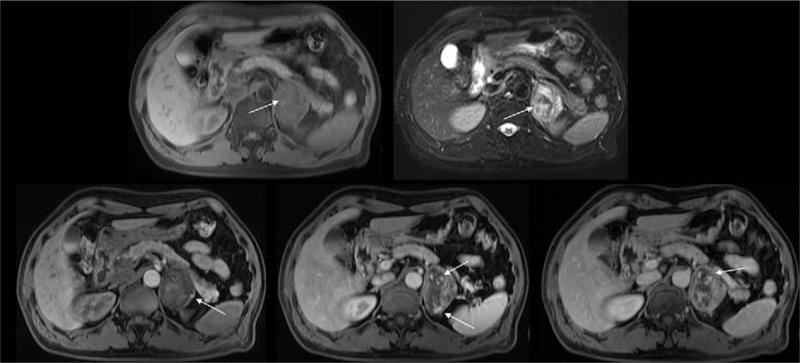

A case report of primary adrenal angiosarcoma as depicted on magnetic resonance imaging.

Medicine (Baltimore). 2017 Nov;96(45):e8551. doi: 10.1097/MD.0000000000008551.

Primary renal angiosarcoma with extensive hemorrhage: CT and MRI findings.

Int Braz J Urol. 2019 Mar-Apr;45(2):402-405. doi: 10.1590/S1677-5538.IBJU.2018.0375.